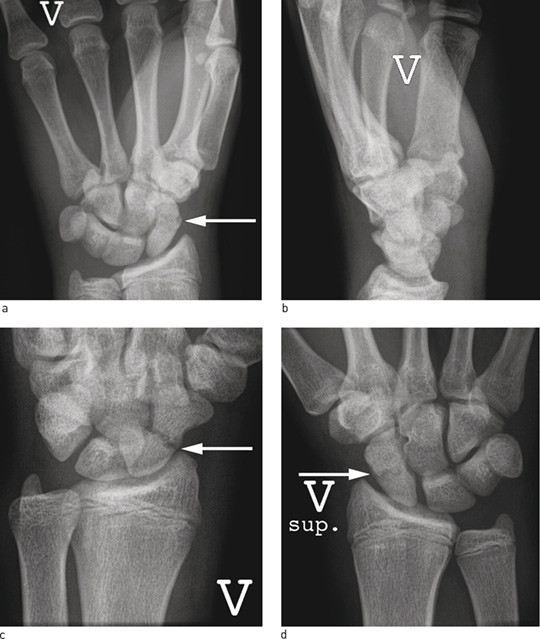

Figure 2  Standard X-ray projections on suspicion of scaphoid fracture, arrow where the fracture is visible. a) Frontal…

Figure 2 Standard X-ray projections on suspicion of scaphoid fracture, arrow where the fracture is visible. a) Frontal projection, b) lateral projection (difficult to identify fracture), c) oblique projection, d) supine projection